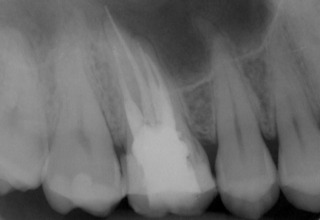

Nach Darstellung aller Wurzelkanaleingänge wird in einem zweiten Schritt das frakturierte Wurzelkanalinstrument dargestellt (Abb. 3 u. 4). Hierfür verwenden wir den Aufsatz 3E des Tigon+. Durch die schmale und lange Form des Instruments erreichen wir einen tiefen und schmalen Zugang.

Sofern es sich um ein kleines Frakturstück handelt, kann es durch aktive Übertragung von Energie des Ultraschalls zu einer Lockerung des Fragments kommen. Lockert es sich nicht, so „umkreist“ man das Instrument vorsichtig, um es anschließend mit einer Spritze gefüllt mit Palavit G zu greifen, zu fixieren und zu entfernen (Abb. 5). Nach Entfernung des Instruments erfolgt eine Kontrollaufnahme (Abb. 6).